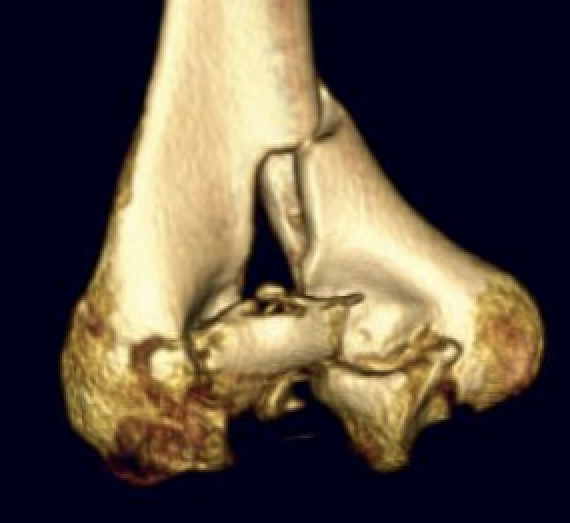

Type C: Complete articular fractures

CT scan